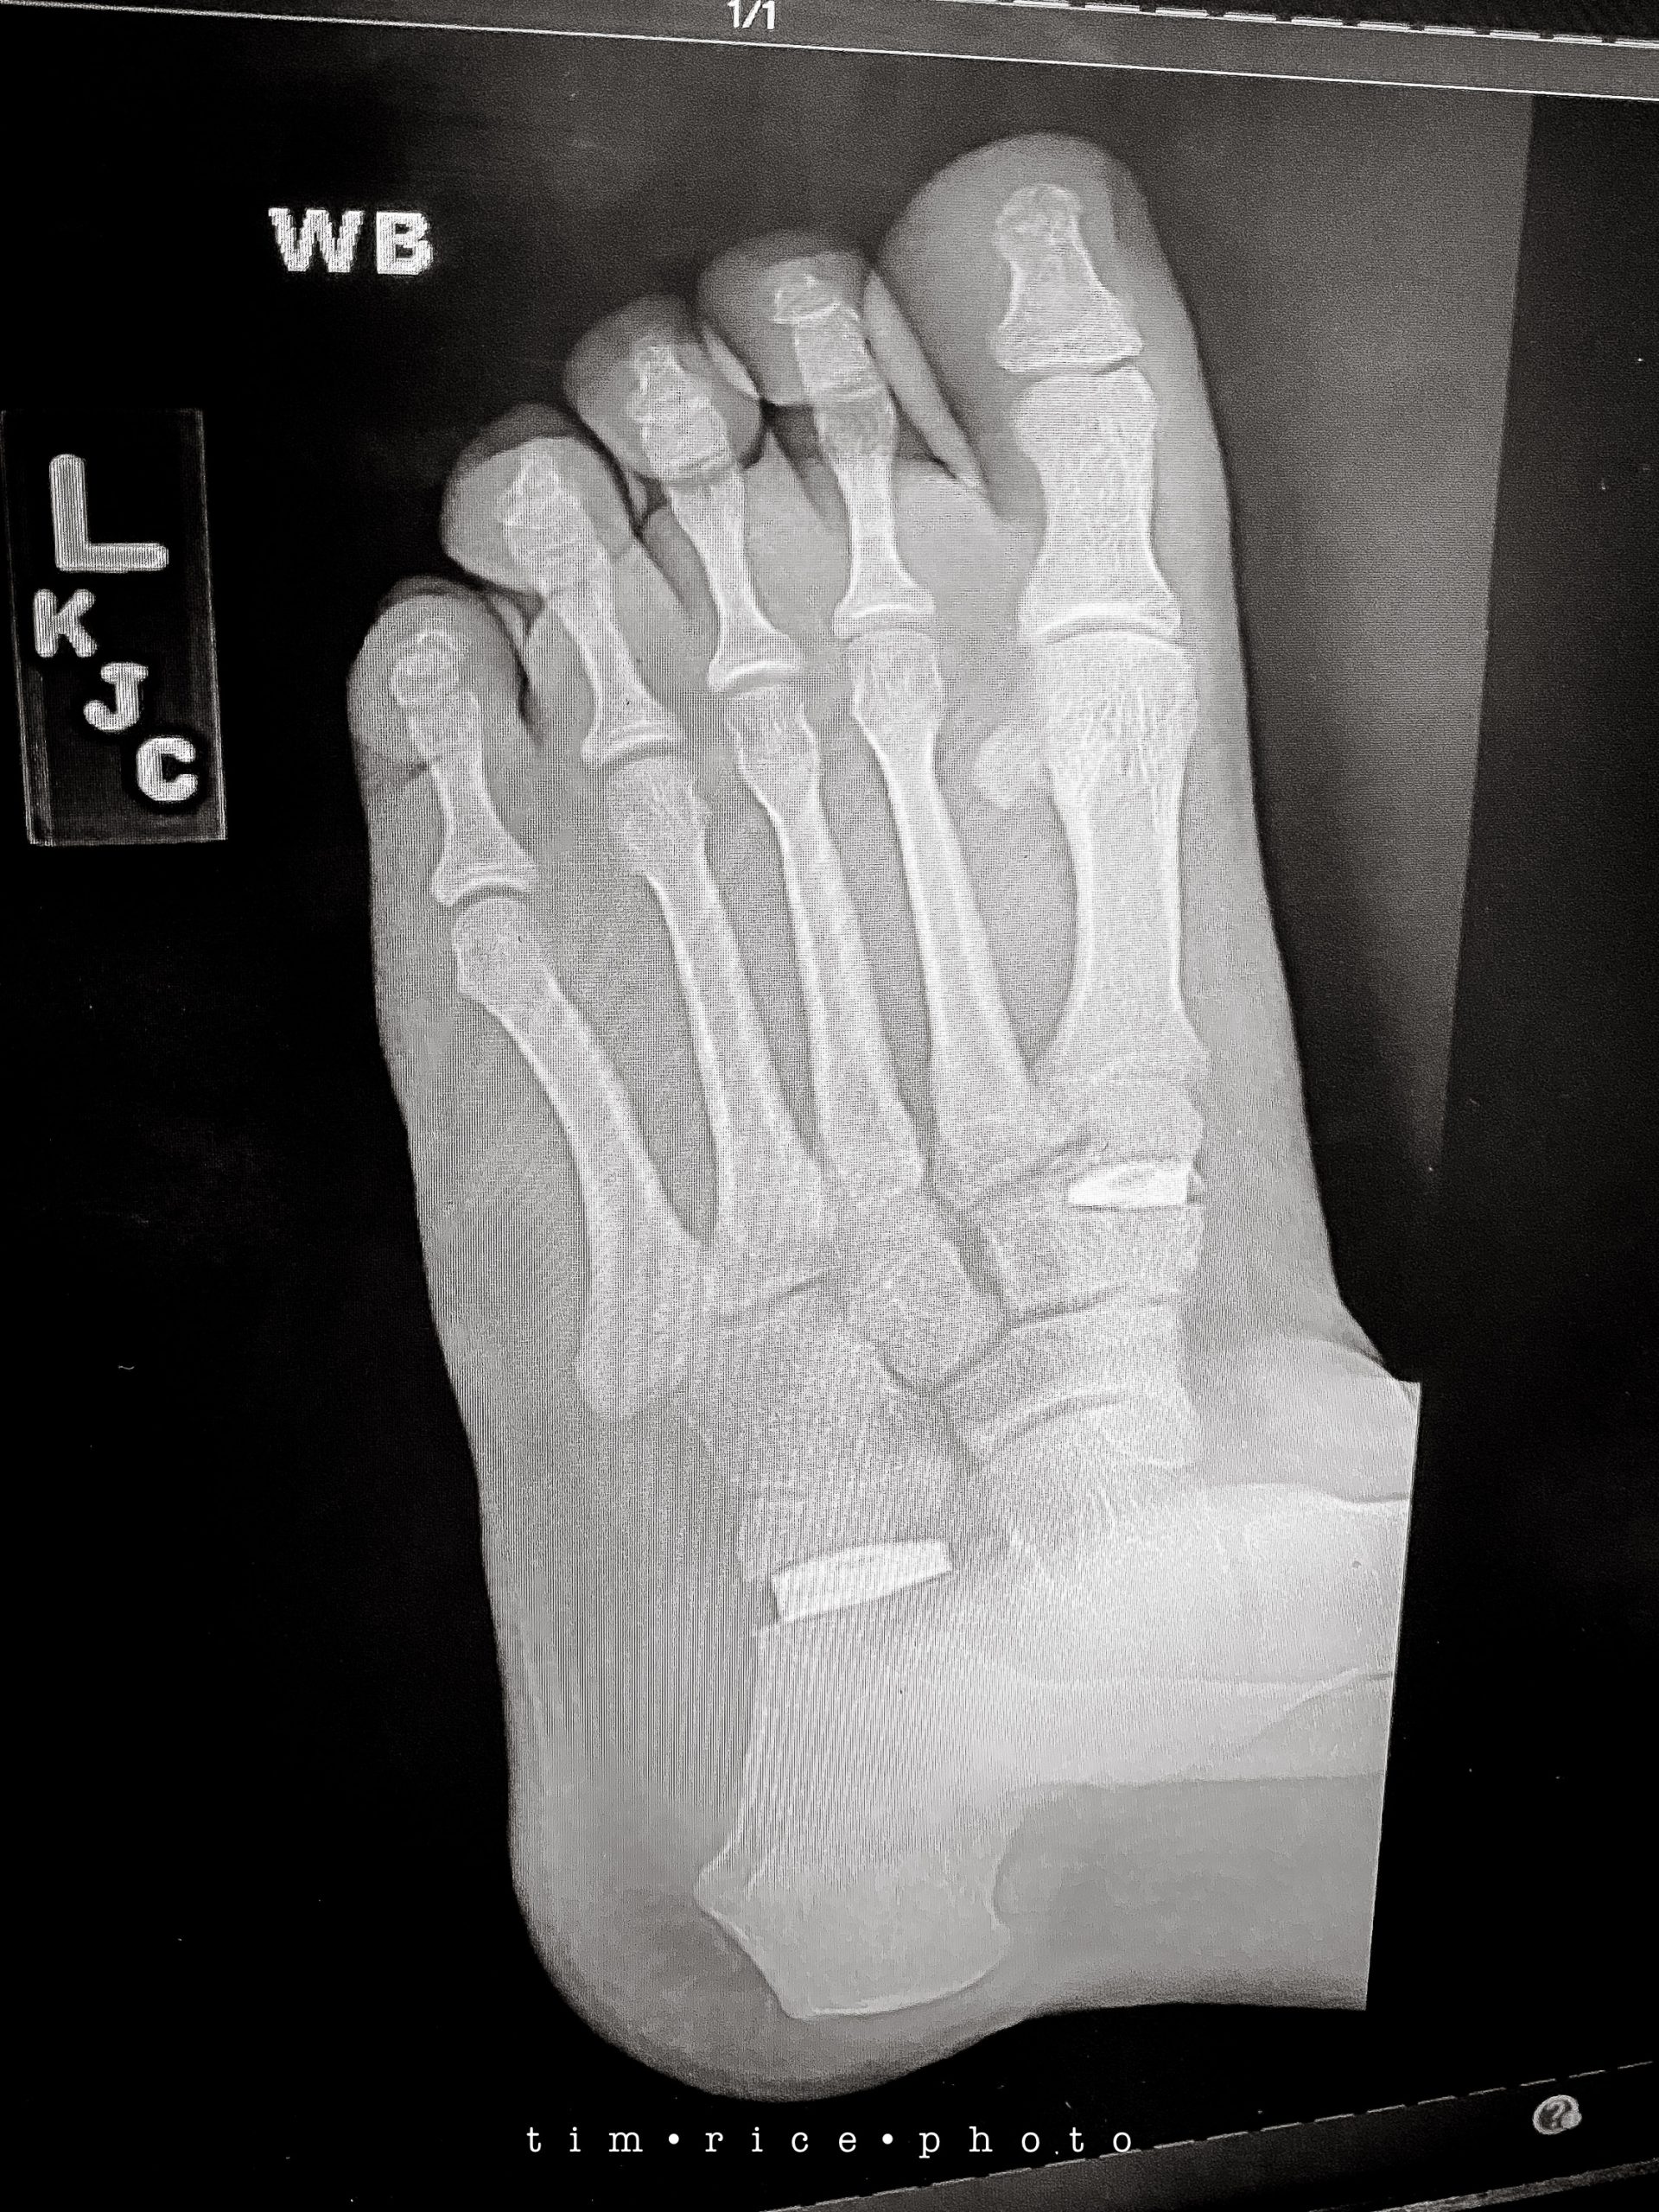

Anyway, I have been asked often for an update on Dan and his LEFT foot. It was four weeks ago today he had his surgery. There are two titanium wedges in between his bones, plus there was a procedure done on his tendon. He has been off his foot 100% since. He can walk with light use of his heel, walking boot, and a crutch as of today. This is huge because he has relied on one of those “kneel-on” leg carts, and that was if he was moving at all. We have not seen him outside of his room too much. All is healing well and slightly ahead of schedule. The before is below, and you can actually see an arch in his foot now. He has never had an arch, hence the years of pain, misery, canes, and ultimately this surgery. This will be life-changing for him, and he has handled it so much better than I would have. Happy to see this all going in the RIGHT direction.